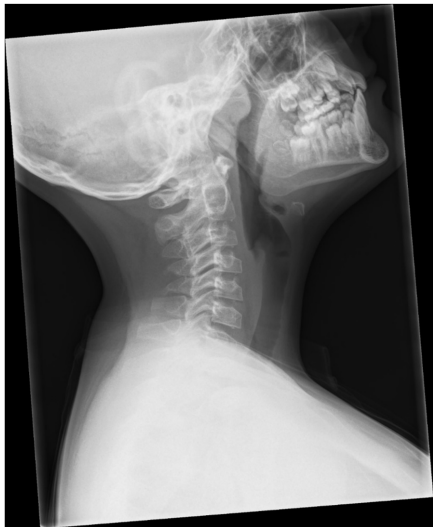

这名10岁男孩的求医之路颇具戏剧性——6岁起出现的颈部僵硬使他不得不像机器人般转动整个上半身来看人。令人困惑的是,他的手指和髋关节完全正常,炎症指标也无异常。MRI揭开了谜底:脊柱呈现奇特的"分叉样"椎间盘结构,伴多节段椎间盘突出。这种影像学表现如同脊柱的"条形码",成为指向PPD的关键线索。基因检测最终锁定CCN6基因纯合突变,而患儿的身高(位于第75百分位)和未受累的小关节,均与经典PPD特征背道而驰。

研究人员采用多模态技术展开探索:全脊柱平片捕捉到椎体前缘喙状改变和扁平椎(platyspondyly);增强MRI发现齿状突周围血管翳却不伴骨髓水肿;基因测序确认CCN6突变位点。这些发现如同拼图般逐步构建出PPD的全新表型谱。

影像学标志性特征